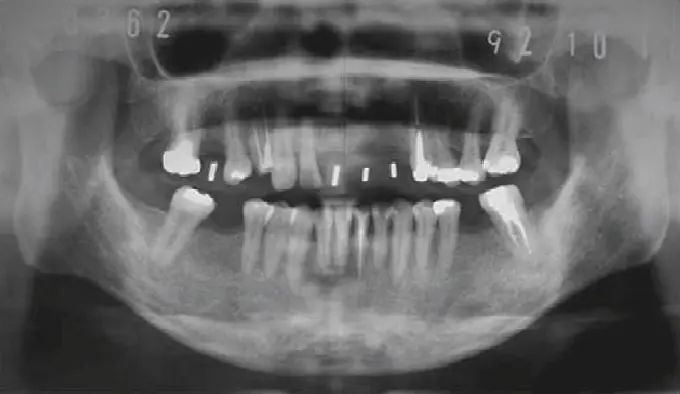

Before anything, I take a 3D CBCT scan of your jaw. This tells me exactly how much bone you have, where nerves are, and whether you need a bone graft. I also check your blood tests — sugar levels, clotting time, Vitamin D, and more. I am strict about this protocol. No shortcuts.

I use CBCT scanning to assess exact bone volume. Even after 5–10 years of a missing tooth, many patients can still get implants with the right approach.